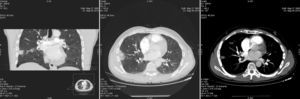

Por ello solicitamos TAC, que evidenció imagen de defecto de repleción en arteria subsegmentaria de lóbulo medio, de localización central, con área de condensación de morfología triangular con base pleural, unido a disminución del calibre de los vasos en esta zona y una menor densidad en dicho lóbulo. Pequeño derrame pleural derecho. Arteria pulmonar de calibre normal (fig. 2). Todo esto es sugestivo de tromboembolismo pulmonar con infarto asociado en lóbulo medio de pulmón derecho.